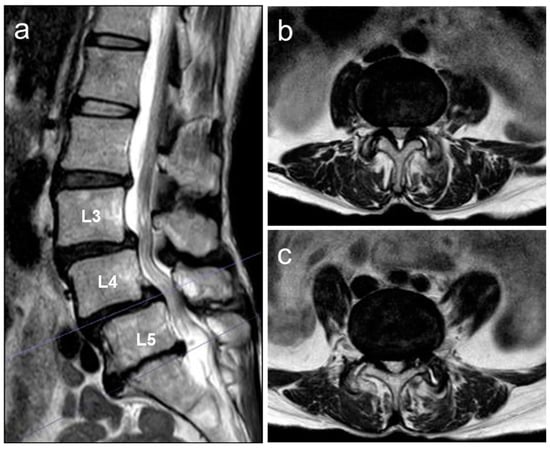

2.2. Image Examinations at First Visit